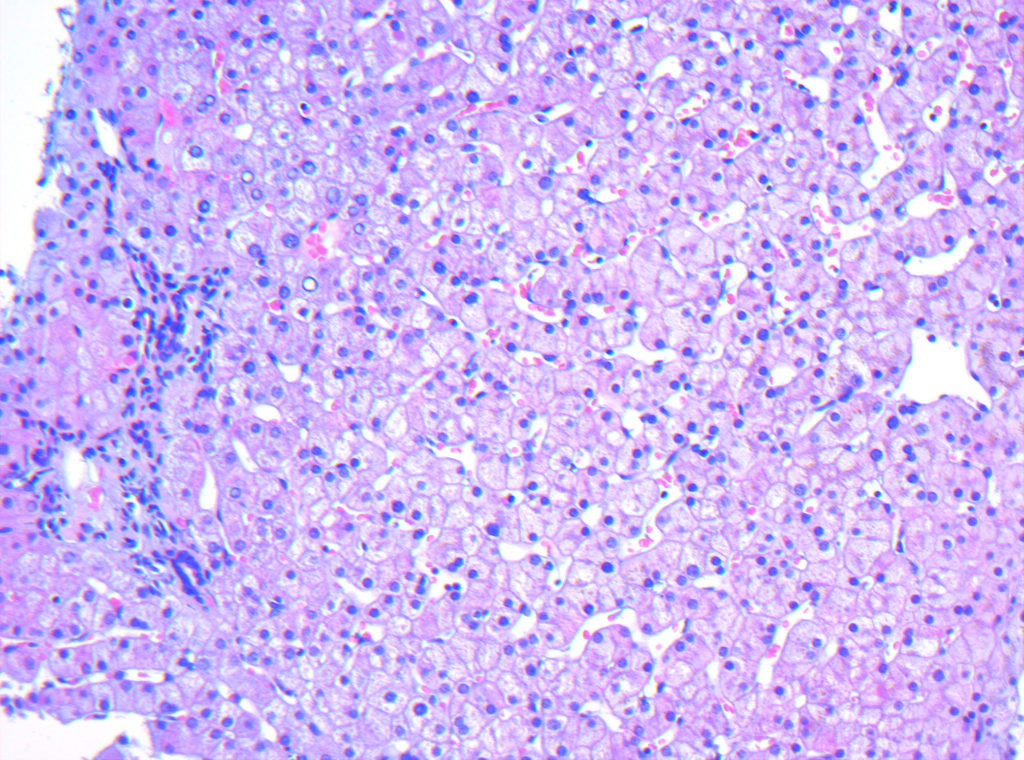

- Histologie: Die Standardmethode einer pathologischen Befundung ist die Anfertigung eines Gewebeschnittes mittels Gefrierschnitttechnik oder Paraffin-Einbettung. Anschließend werden unterschiedliche Färbungen angewendet um eine optimale Diagnostik sicherzustellen.